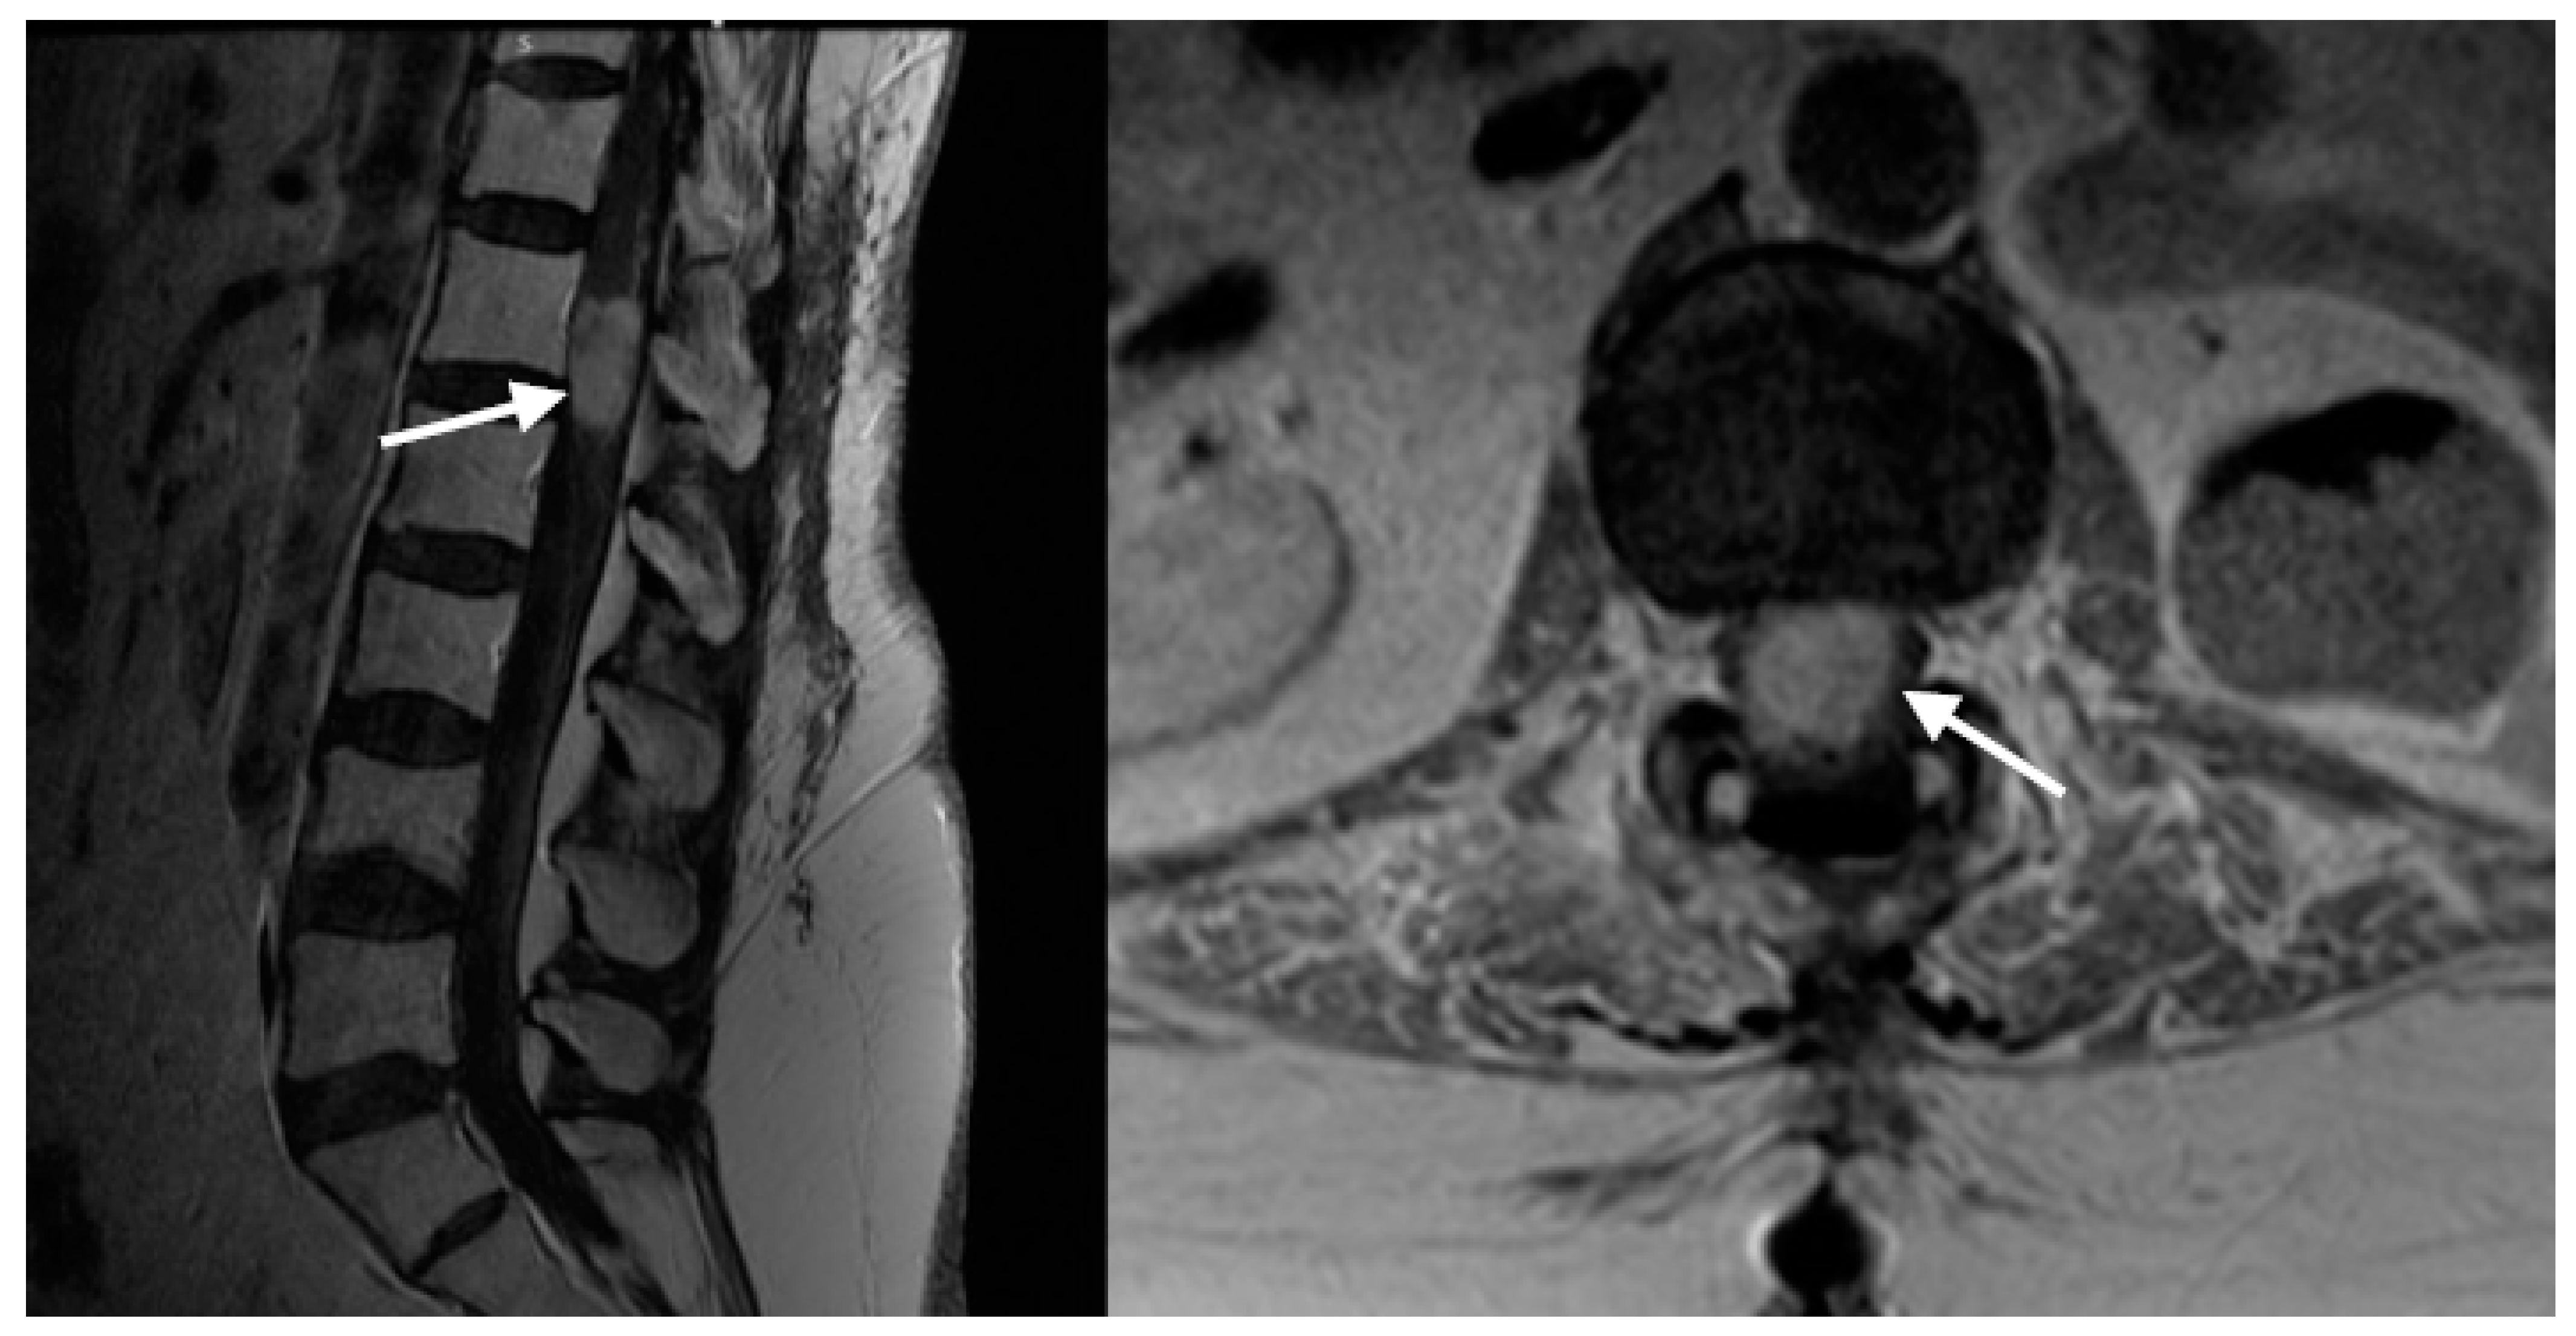

2.3. Case Illustration